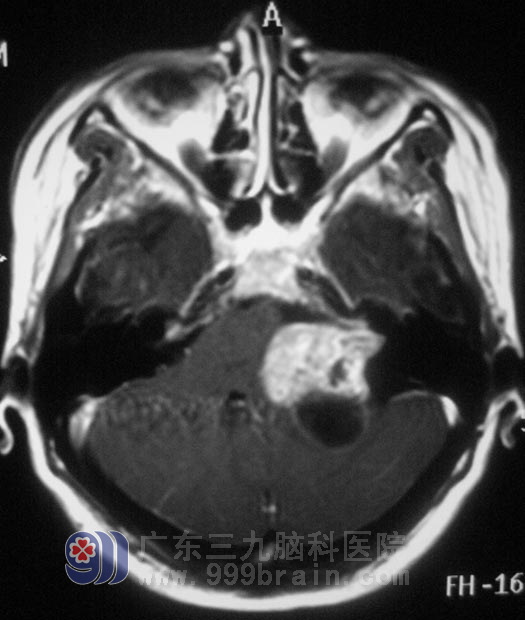

李女士是公司的财务人员,一个月前出现头痛,以左枕部明显,呈阵发性钝痛,以为是年底工作忙,劳累过度所致,休息一周后,头痛也不见好转。当地医院行头颅CT检查,结果示:“左侧小脑、枕叶交界处低密度影,约2.9cm×2.3cm;梗阻性脑积水”。

12月16日,由广东三九脑科医院综合神经外科 鲁明主任主刀,在全麻下行“左侧桥小脑角区肿瘤切除术”。显微镜下见黄白色肿瘤组织,质软,血供丰富,面神经位于肿瘤前下方,副神经、迷住神经、舌咽神经位于肿瘤后下方,神经组织形态菲薄。在显微镜下利用超声刀分块切除,见肿瘤深入内听道,磨钻磨除部分内听道,切除内听道内肿瘤组织,对中后组颅神经保留完整,手术顺利结束。术后李女士经过一段时间的恢复后,梗阻性脑积水情况得到了缓解,听力保存完好,副神经均没有受到影响。术后病理结果为:(左侧桥小脑角)符合听神经瘤。http://www.999brain.com/